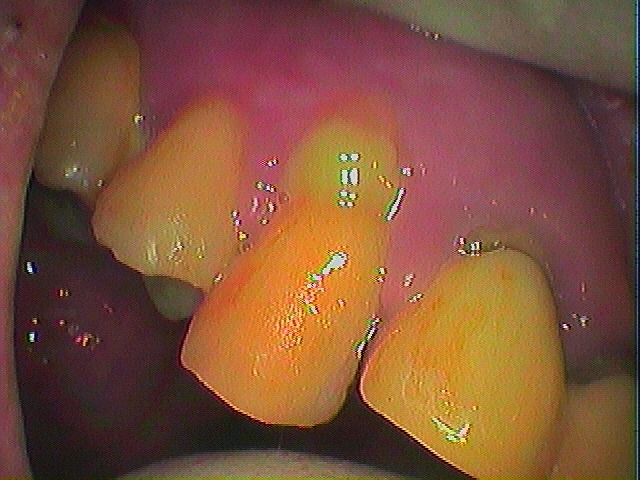

右上の4番部が原因で歯周病より歯茎から排膿が止まらないケース

初期治療をおこなうのですが、、、

排膿が止まりません

4番部が打診も強く排膿も酷かったので根管治療を行っていきました